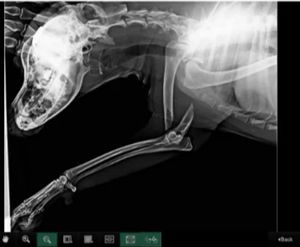

Ola meu nome é Tais , sou de Joinville- sc preciso do valor para fazer a cirugia da pata traseira do manflei, cachorro que resgatei final do ano passado  que estava abandonado na chuva na frente do meu portão,   Encontrei  ele com a pata quebrada e muito assustado com marcas de queimaduras  tentei  buscar os donos contatei diversas páginas e não achei ninguem com condiçoes que pudesse adotar ele , sendo assim resolvi ficar com ele mas não tenho como pagar a cirurgia . peço a ajuda de vocês pois não tenho condições  o intuito da cirurgia e dar qualidade de vida para o manflei e tirar a dor que ele possui . muito grato pela atenção  , qualquer 1 real ja ajuda